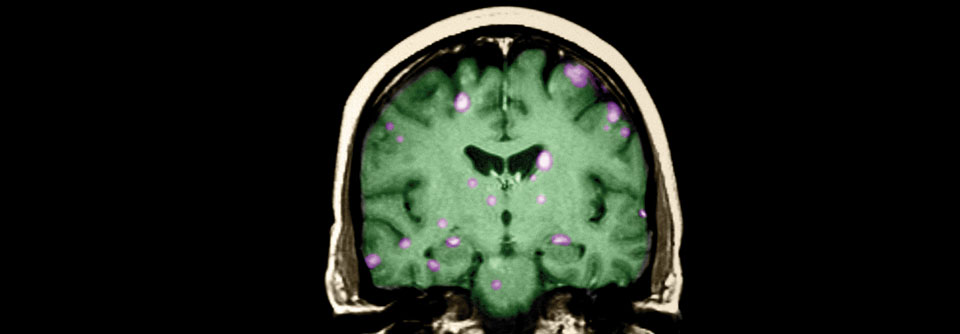

Mammakarzinom Verlängertes PFS bei Patienten mit ZNS-Metastasen

Die Therapie mit Trastuzumab-Deruxtecan zeigte in der Zweitlinie von Erkrankten mit metastasiertem HER2-positivem Mammakarzinom einen in dieser Größenordnung noch nicht gesehenen Vorteil gegenüber T-DM1. Neue Subgruppen-Analysen bestätigten jetzt diese Überlegenheit. Eine weitere Studie liefert zudem Hinweise auf die Aktivität der Substanz bei geringer oder fehlender HER2-Expression.

Das Antikörper-Wirkstoff-Konjugat Trastuzumab-Deruxtecan (T-DXd) ist zugelassen für Patienten mit fortgeschrittenem HER2+ BrustkrebsKrankheitsbild Detailseite. In der DESTINY-Breast03-Studie wurde die Substanz gegen ihren Vorgänger Trastuzumab-Emtansin (T-DM1) bei 524 mit Trastuzumab und einem Taxan vorbehandelten Personen mit meta­stasiertem HER2+ Mammakarzinom geprüft. Das Risiko für Krankheitsprogression oder Tod verringerte sich um 72 % (HR 0,28) in der Interventionsgruppe.1

In einer neuen Analyse bestätigte sich die signifikante Verbesserung von medianem progressionsfreiem Überleben (PFS) und objektiver Ansprechrate (ORR) in allen zu Studienbeginn definierten Subgruppen.2 Wie Prof. Dr. Sara A. Hurvitz von…